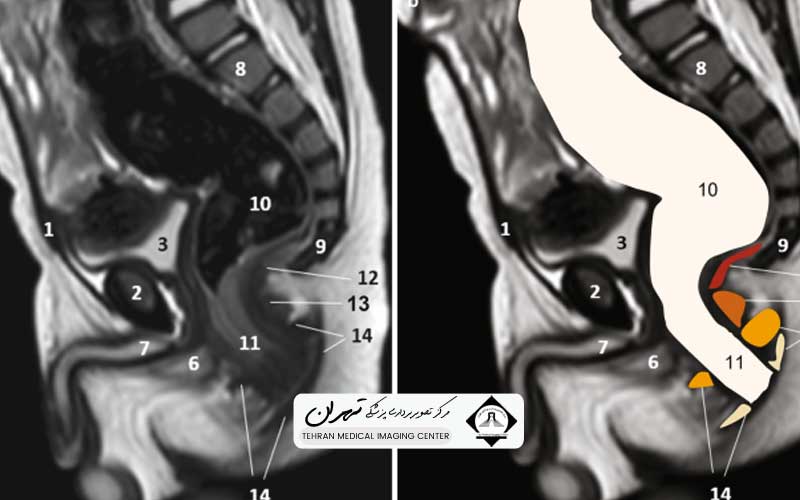

ام آر آی کمر و لگن یک روش تصویربرداری پزشکی پیشرفته است که از میدان مغناطیسی قوی، امواج رادیویی و کامپیوتر برای تولید تصاویر مقطعی با وضوح بالا از ناحیه پایین کمر (مهرههای کمری و ساکرام) و ساختارهای استخوانی و بافت نرم لگن استفاده میکند. هدف اصلی این روش، ارائه یک نقشه دقیق و سهبعدی از این ناحیه حیاتی بدن است.

هنگامی که هستهها به حالت اولیه باز میگردند، سیگنالهایی ساطع میکنند که توسط دستگاه دریافت شده و کامپیوتر بر اساس تفاوت این سیگنالها (که ناشی از تفاوت در نوع بافت است)، تصاویر دقیقی از دیسکها، نخاع، عضلات و استخوانها میسازد. این تصاویر برای تمییز دادن آسیبهای بافت نرم از ساختارهای استخوانی بسیار مؤثر هستند.

به دلیل وضوح بالای تصاویر بافتهای نرم، ام آر آی کمر و لگن یک ابزار تشخیصی بسیار حیاتی برای بررسی ریشههای عصبی در کانال نخاعی، تشخیص فتق دیسک یا تنگی کانال نخاعی، و همچنین ارزیابی وضعیت مفصل ران و سایر مفاصل لگنی است.

یکی از مهمترین کاربردهای ام آر آی کمر و لگن، بررسی دقیق ناهنجاریها و آسیبهای ستون فقرات کمری است. دردهای ارجاعی به پاها، که اغلب نشانهای از درگیری عصب سیاتیک هستند، به وضوح توسط این روش قابل ریشهیابی میباشند.

اصلیترین کاربرد تشخیصی، ارزیابی دیسکهای بین مهرهای است. ام آر آی کمر و لگن میتواند با دقت بینظیری، فتق دیسک (برآمدگی یا پارگی دیسک)، میزان فشار دیسک بر روی ریشههای عصبی مجاور و وجود دیسکوپاتی (بیماری تخریبی دیسک) را نشان دهد، که در این امر، سایر روشهای تصویربرداری ناتوان هستند.